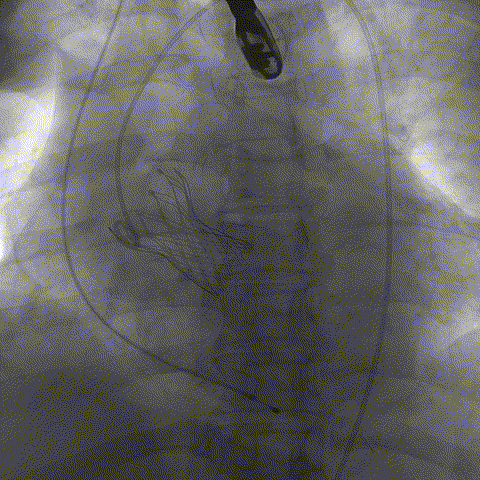

手术影像:

工作位造影位置良好